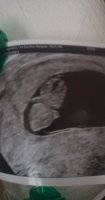

Dette bildet er fra innvendig mellom uke 7 og 8.